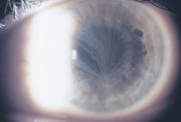

- All 3 forms can present with severe corneal clouding that mostly involves the stroma (sparing the endothelium and Descemet's membrane.

- Needle-shaped crystals in the cornea can be detected on slit-lamp biomicroscopy

- Crystal can be found in all layers of the cornea (starts in the anterior peripheral stroma

- Increased cornea thickness (due to accumulation of crystals)

- Bilateral lipid and cholesterol crystals deposition in the corneal stroma, full-thickness involvement can occur. 50% of patients have crystals.

- Corneal stromal haze due to focal deposits of lipid